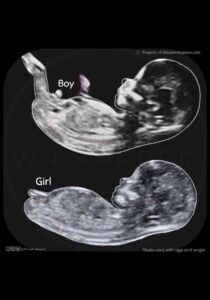

Aşağıdaki resimde girl yazan ultrasonda kız bebek resmidir.